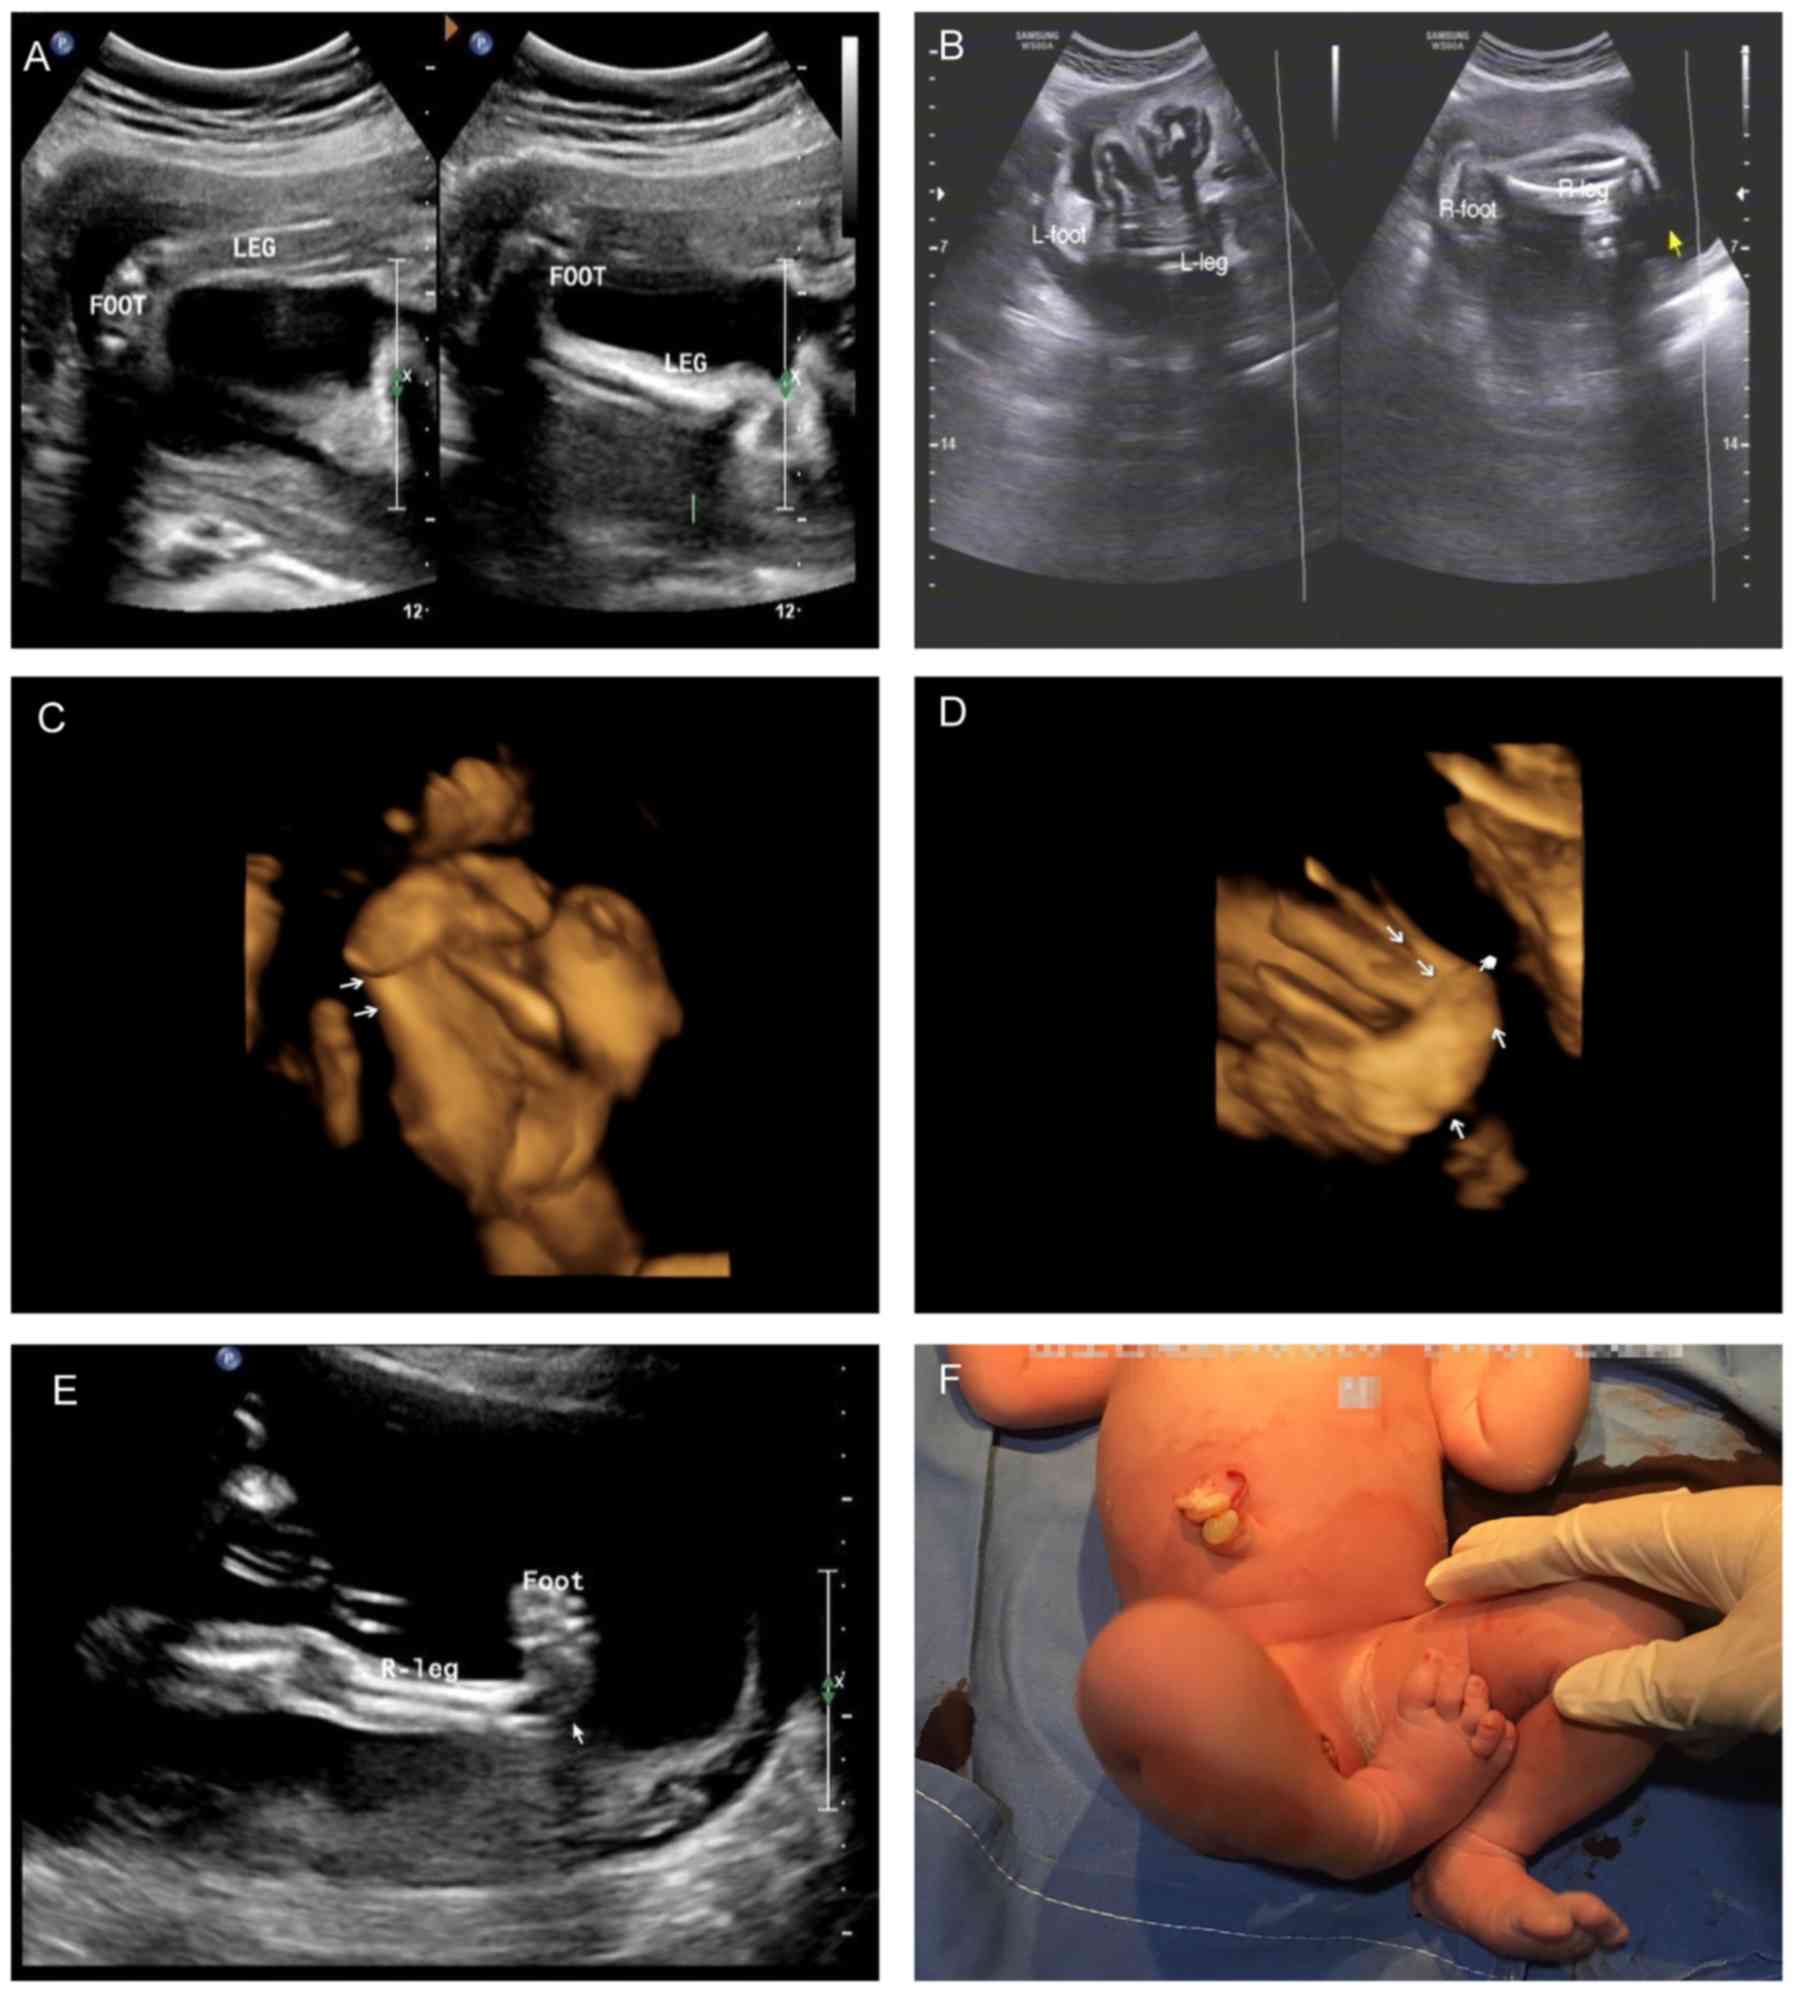

The main clinical data are presented in Table I. All the subjects were patients with ICTEV with no family history of the disease (Table I). The parents had no adverse habits, for example, smoking. Representative clinical and ultrasonic illustrations are presented in Fig. 2.

Figure 2.

Representative clinical and ultrasonic images of the recruited subjects. (A) Case 1: Bilateral CTEV at 22 gestational weeks. (B) Case 2: Bilateral CTEV at 20 weeks. View (C) 1 and (D) 2 of case 3: Bilateral CTEV at 21 weeks. (E) Case 8: Unilateral (right) CTEVat 23 weeks. (F) Case 9: Unilateral (right) CTEV at birth. Arrows indicate the affected parts. CTEV, congenital talipes equinovarus.